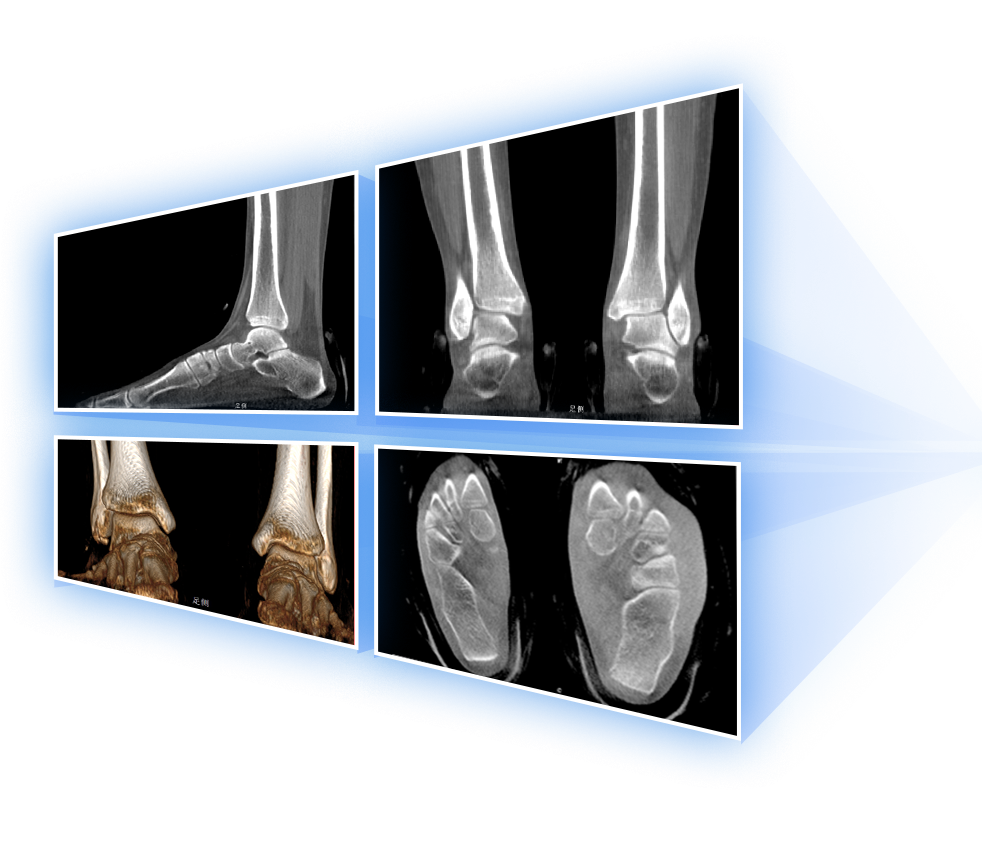

· 补位CT,提供负重位三维影像

· 引领普放走向三维精准诊断时代

填补常规CT/MR空白

助力术前规划和术后评估

足踝

精准诊断

手术方案规划

术后随访